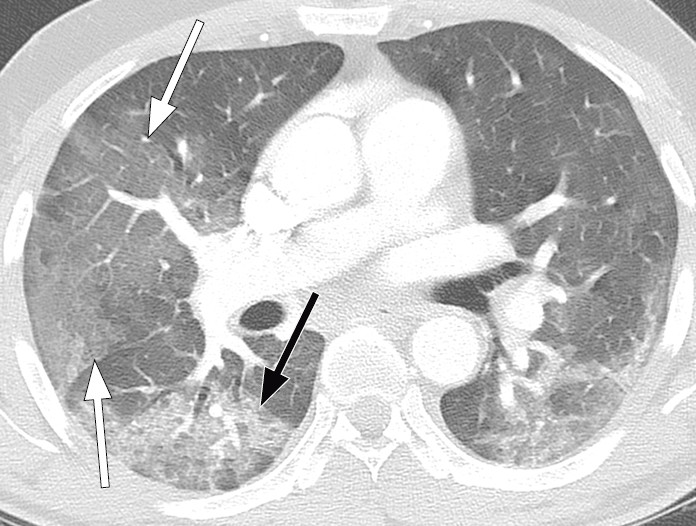

Typical CT findings vary with symptom duration and can be divided into three stages: an early phase, an intermediate phase that extends from 3–5 days after symptom onset, and a late phase.

There are not always CT findings the first few days after symptom onset. In a material with symptomatic, but unspecified patients, 56 % had normal CT findings within two days of symptom onset (12), declining to 9 % 3–5 days after symptom onset and 4 % 6–12 days after symptom onset. The frequency of findings varies with the severity of the disease. Initial diagnostic imaging yielded normal findings for 18 % in a cohort of patients who were not severely ill, but in only 3 % of patients who were (15). Typical CT findings are multiple, bilateral ground-glass opacities with peripheral distribution, most frequently located in the lower lobes. In the intermediate phase there are increasing amounts of consolidation and affection of several lobes, and increased septation with crazy paving as sign of interstitial affection. In the late phase there is increasing total extension, but ground-glass opacities and consolidation are still the dominant findings (12, 16). Figures 4, 5 and 6 show typical CT findings in different phases of COVID-19.

In a severe disease course, distortion of the lung architecture, traction bronchiectasis, enlarged lymph nodes and pleural fluid can be detected. These are findings that are not specific for COVID-19 (17).